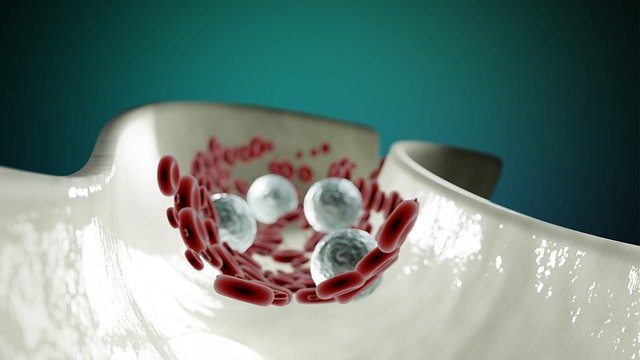

“Κατά την απώλεια αίματος, ο εγκέφαλος συντονίζει μια καρδιαγγειακή απόκριση που υποστηρίζει τη ροή του αίματος σε κρίσιμα όργανα, όπως η καρδιά και ο εγκέφαλος”, δήλωσε ο ερευνητής George Souza, Ph.D., του Τμήματος Φαρμακολογίας της UVA. “Η μελέτη μας δείχνει ότι η καρδιαγγειακή απόκριση στην απώλεια αίματος εξαρτάται από αλλαγές στη δραστηριότητα μερικών εκατοντάδων νευρώνων στο εγκεφαλικό στέλεχος”. Τα νέα αποτελέσματα, από τον Stephen Abbott, Ph.D., και τους συνεργάτες της UVA, ρίχνουν φως σε μια σημαντική διαδικασία που χρησιμοποιεί το σώμα για να διατηρήσει την αρτηριακή του πίεση. Οι νευρώνες Abbott και η ομάδα του περιγράφουν – γνωστοί ως “αδρενεργικοί νευρώνες C1” – παρακολουθούν την αρτηριακή πίεση και εναλλάσσονται σε δράση κατά την απώλεια αίματος.

Όταν οι νευρώνες ανιχνεύουν απώλεια αίματος, αυξάνουν τη νευρική δραστηριότητα που συστέλλει τα αιμοφόρα αγγεία και διατηρεί τη σωστή αρτηριακή πίεση. Οι επιστήμονες μπόρεσαν να το προσδιορίσουν χρησιμοποιώντας προηγμένη απεικόνιση και μια τεχνική που ονομάζεται οπτογενετική που επιτρέπει τον απομακρυσμένο έλεγχο των νευρώνων με χρήση φωτός. Η έρευνά τους αποκάλυψε ότι οι νευρώνες C1 είναι υπερκινητικοί κατά την απώλεια αίματος και αυτό διατηρεί την αρτηριακή πίεση. Αλλά αυτοί οι νευρώνες γίνονται ανενεργοί με σοβαρή απώλεια αίματος, με αποτέλεσμα την καρδιαγγειακή κατάρρευση. Η μη αντιρροπούμενη αιμορραγία είναι το προοίμιο του αιμορραγικού σοκ, κατά το οποίο το σώμα αρχίζει να κλείνει. Αλλά οι επιστήμονες ανακάλυψαν ότι η επανενεργοποίηση των νευρώνων C1 σε αρουραίους εργαστηρίου αποκατέστησε τόσο την αρτηριακή πίεση όσο και τον καρδιακό ρυθμό.